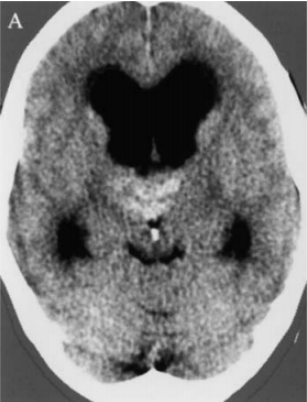

Bella雙丘腦海綿狀血管瘤導(dǎo)致Monro雙孔腦脊液阻塞、顱內(nèi)壓升高。由于由于腦脊液通路在Monro孔、Sylvius導(dǎo)水管受阻,因此需要先放置腦室-腹腔分流術(shù)治療梗阻性腦積水。在隨后的手術(shù)中,巴特朗菲教授較終通過經(jīng)胼胝體入路全切病變,手術(shù)成功,無其他任何神經(jīng)功能缺損。

術(shù)后顱腦CT